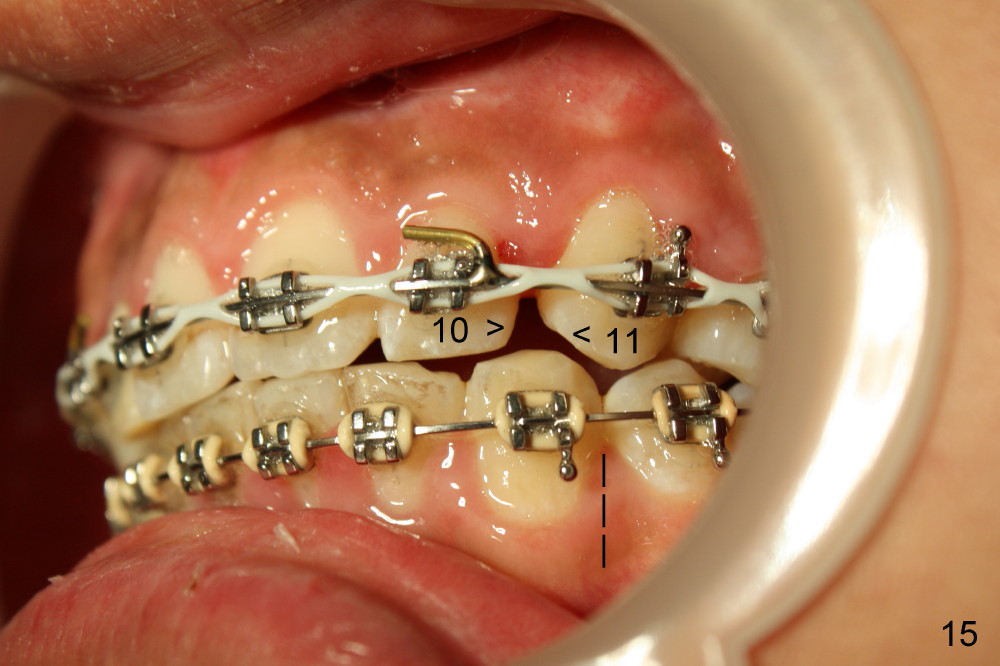

Fig.13-15 shows the upper incisors totally 4.5 month of retraction. The upper left canine (Fig.15: #11) seems to be distalized too much, as compared to the dashed line. Therefore whole arch power chain is placed with an intention to bring the canine mesially (arrowhead) while continue distalizing the incisors (including #10 (arrowhead).